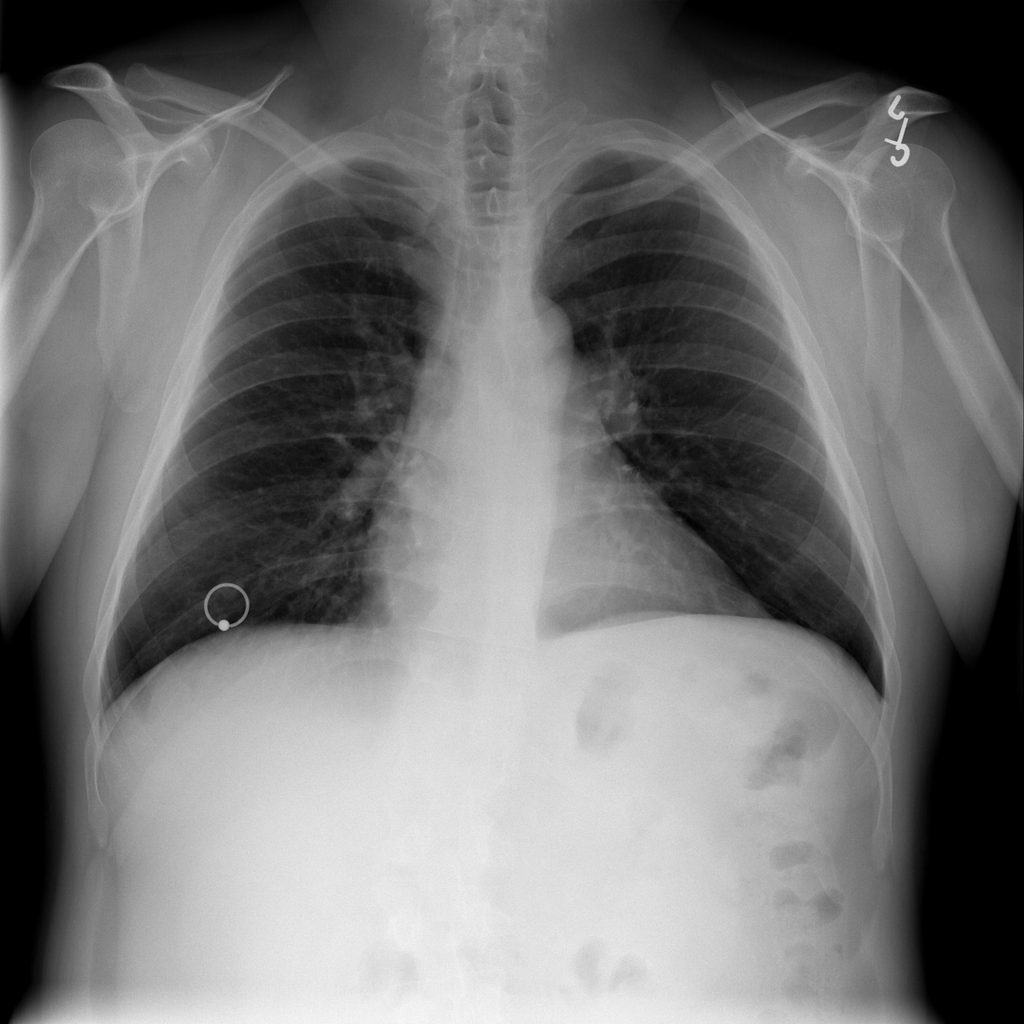

Showing up to 90 reference images for Pneumonia.

PAT-C0E5 · IMG-015Pneumonia

PAT-C0E5 · IMG-015

AP